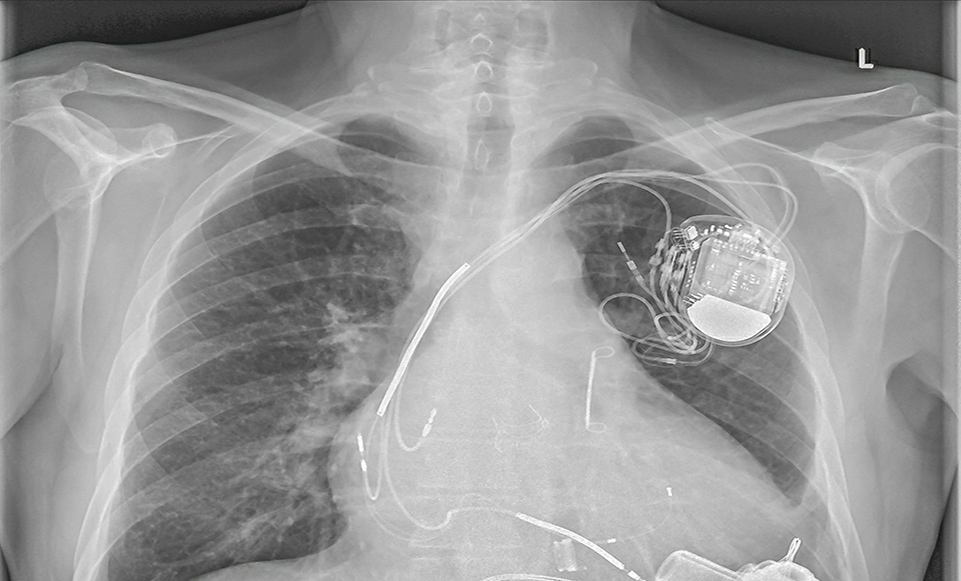

为了更好治疗房颤并预防中风,常将“房颤消融”和“左心耳封堵”两者术式结合形成“一站式”。简单来说,消融手术就像是给心脏的“电路”做修理,用特殊的能量去消除那些让心脏乱跳的异常信号,让心脏恢复正常的跳动节奏;而左心耳封堵手术则是给心脏里容易长血栓的地方(左心耳)装上一个“小伞”,把血栓堵在里面,不让它跑出来引发中风。目前消融方式包含有射频消融、冷冻球囊导管消融及电脉冲消融。